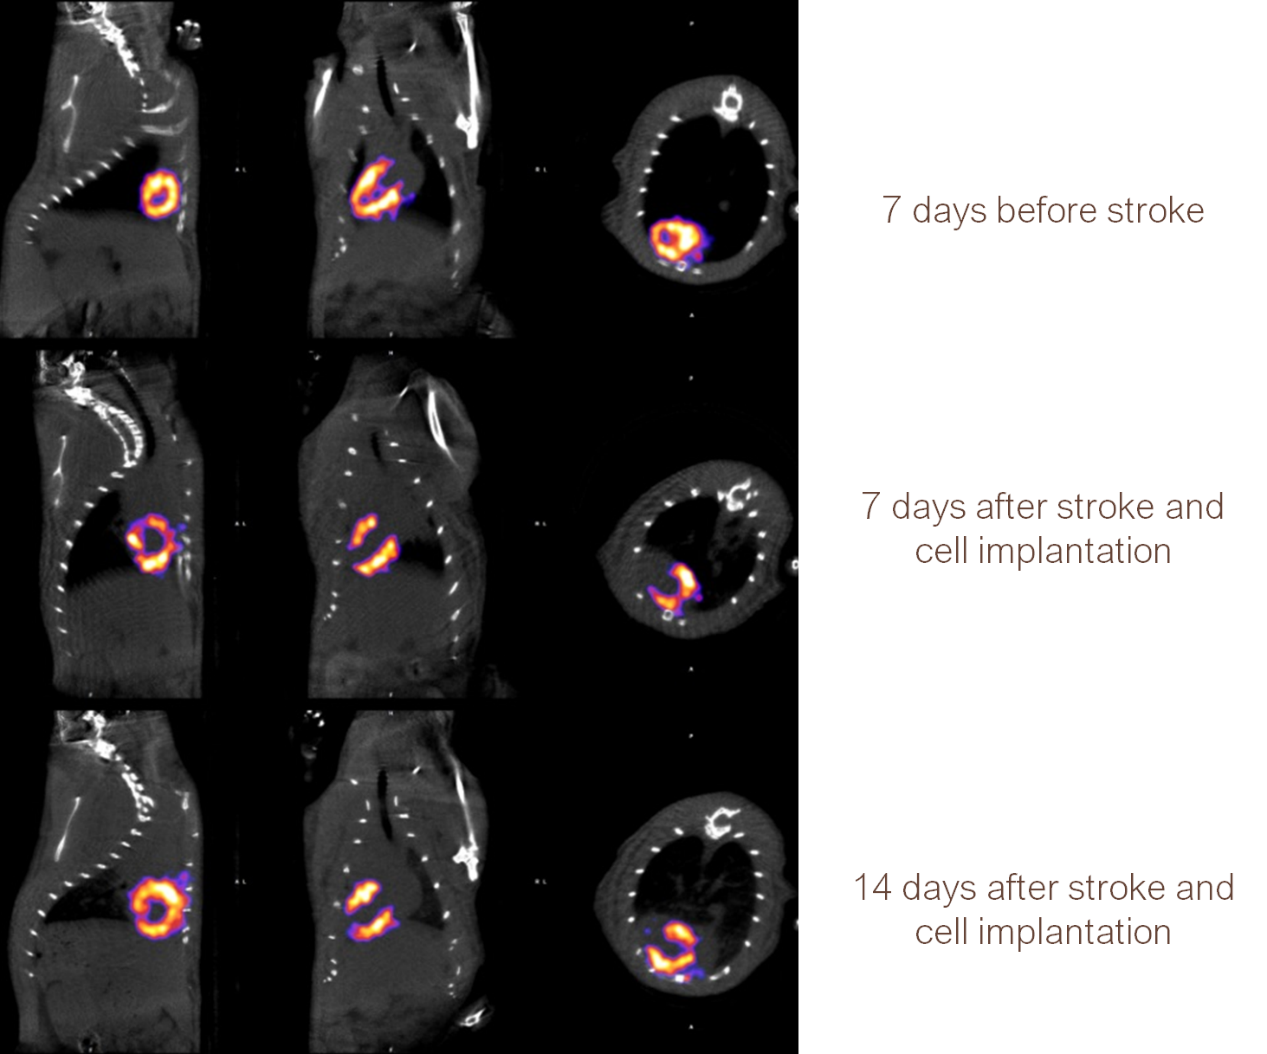

大鼠心血管中風(fēng)模型,中風(fēng)前后及用藥后,觀察心臟血流狀態(tài)。

大鼠心血管成像.png